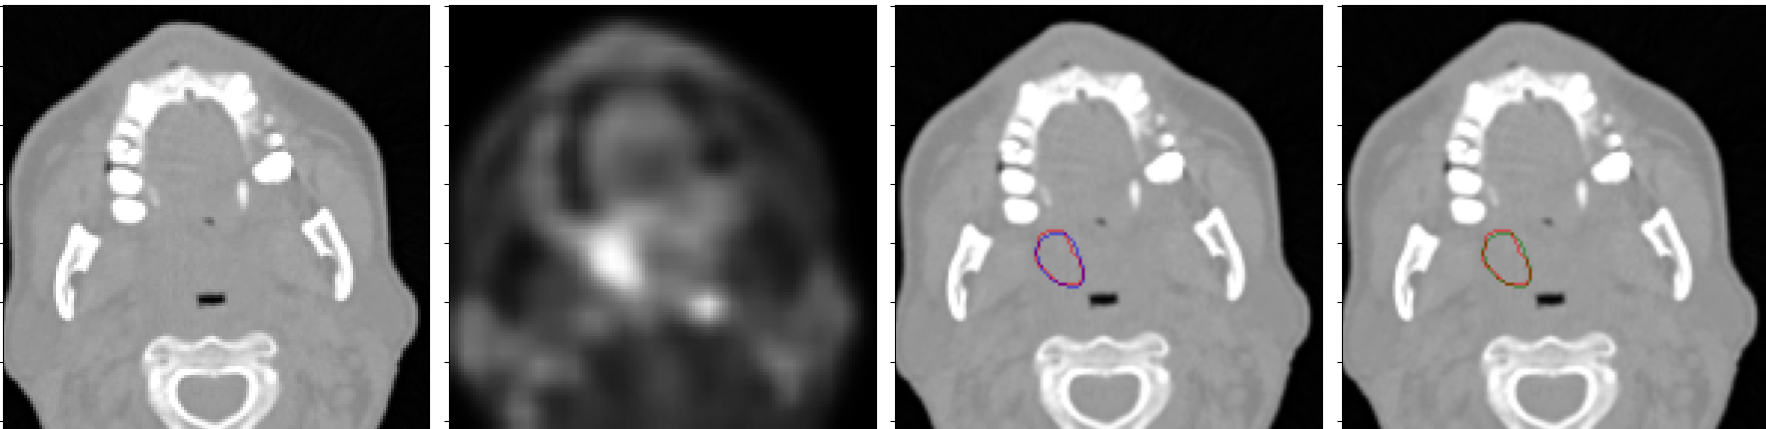

We trained the 3D NormResSE-Unet3+ on a leave-out one center, and we performed model ensembling by averaging the predictions on the test set of the 5 models trained (see Fig. 3 and Tab. 1).

An example of a good quality segmentation map predicted by our model is shown in Fig. 3 (the first row).

An example of the predicted segmentation map, which benefited from the CRF post-processing to reduce false positives is shown in Fig. 3 (the second row).